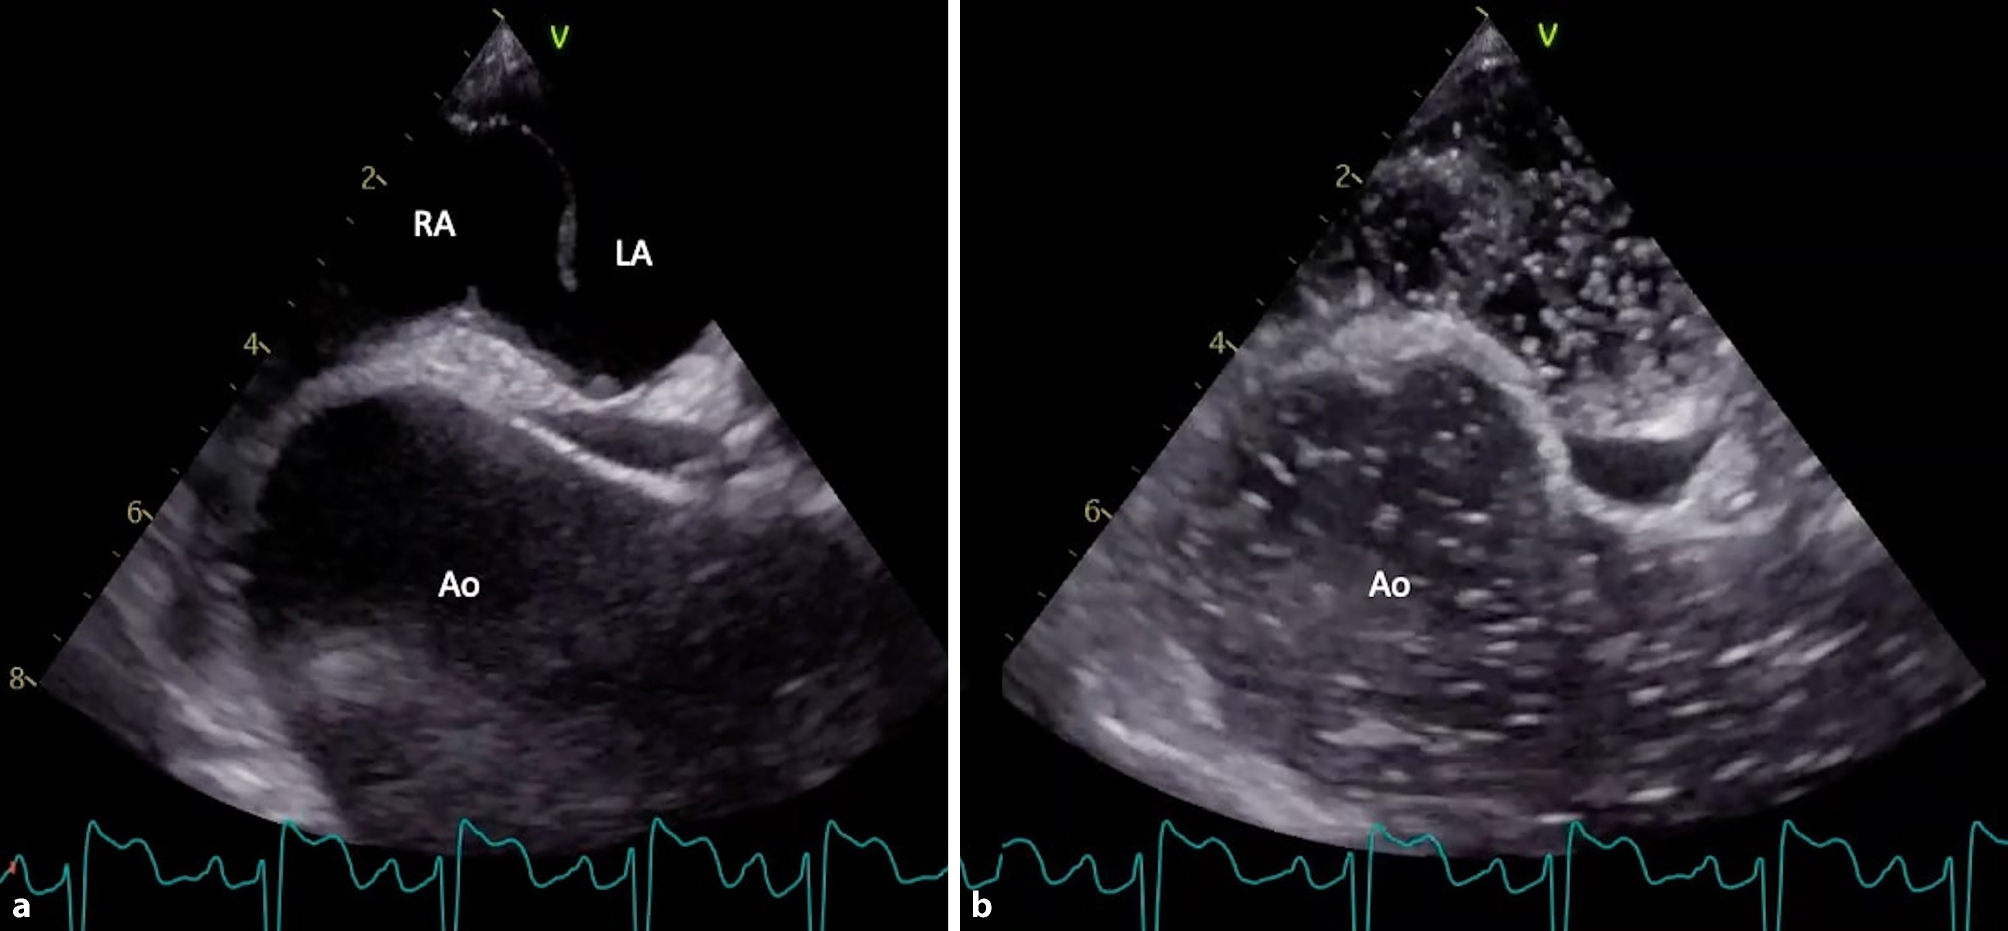

Pulmonary computed tomography angiography revealed a 50-mm ascending aortic aneurysm with no evidence of pulmonary embolism. A transoesophageal echocardiogram showed the aneurysm compressing the right atrium, distorting the atrial septum, and stretching a patent foramen ovale (PFO) (Fig. 1a), causing a significant right-to-left shunt (Fig. 1b; see Supplementary Material, video 1). This confirmed platypnoea-orthodeoxia syndrome (POS).

Fig. 1

Ascending aortic aneurysm, compressing the right atrium and stretching a patent foramen ovale (a); large right-to-left shunt visualised on bubble study (b)